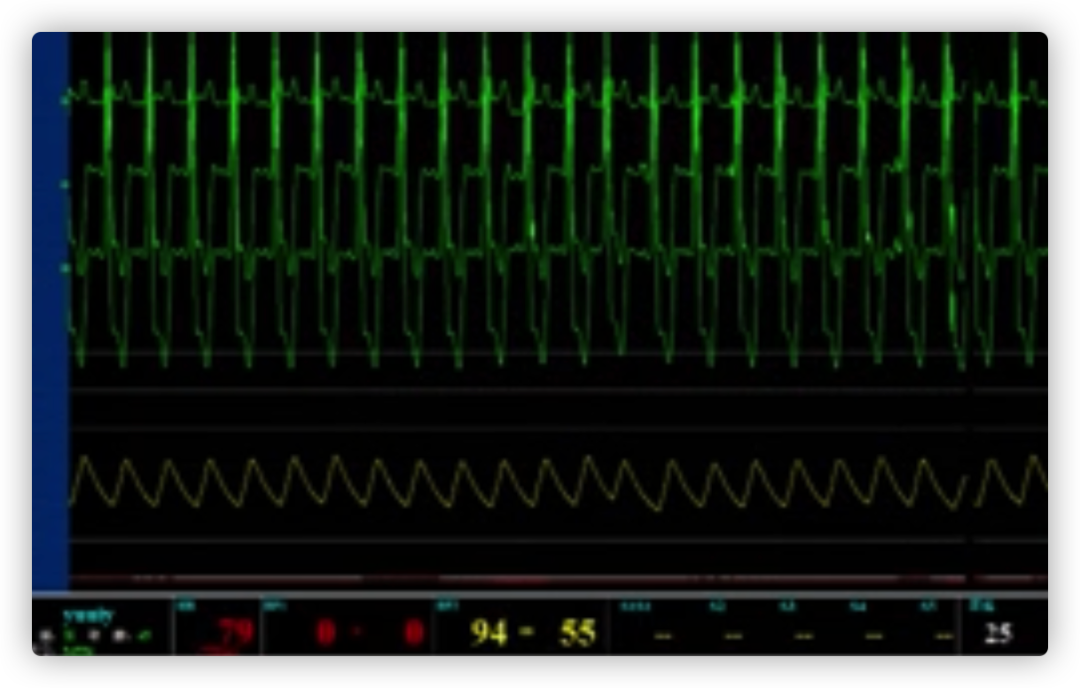

ECG术前

ECG术后即刻

ECG出院时